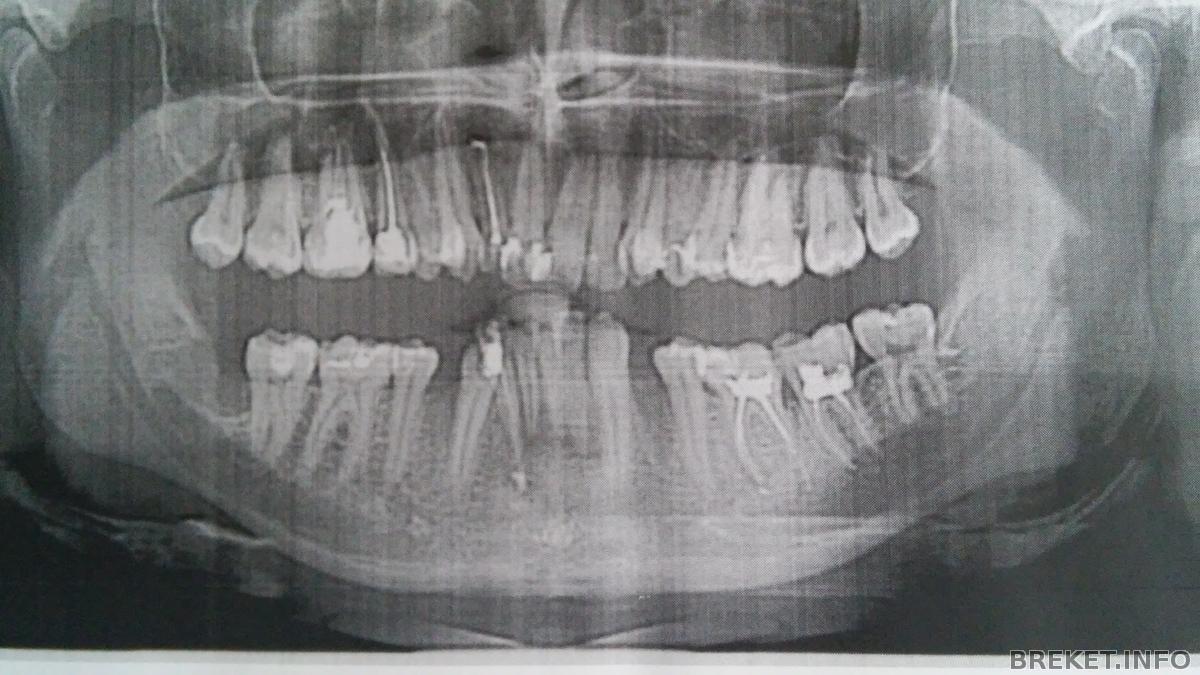

Скриншоты томографии верхней челюсти:

Скриншоты томографии нижней челюсти:

В очередной раз сегодня посетил ортодонта. Носить железки на зубах придется 3 года. Три!!! А затем лет шесть ретенции. После таких цифр попытки врача хоть как-то меня подбодрить были тщетными - я был в ступоре. Говорит, что кость уже сформировалась, поэтому такие длительные сроки. По стоимости полный курс лечения "под ключ" обойдётся примерно в 53 т.р, плюс к этому на ВЧ поставят какую-то дополнительную железку за 3 т.р (оплата за неё будет отдельно, т.к. изготавливаться она будет в сторонней лаборатории). Прайс пока не изменился, по всей видимости из-за того, что гос.поликлиники не вправе повышать цены на материалы, которые ещё есть в наличии на складе. Повышение будет уже на новые партии брекетов, мне это не грозит. Вновь сделали слепок, но уже только верхней челюсти - для изготовления железяки. После чего между зубами сверху просунули резиновые сепараторы. Ах да, к тому же на томограмме подтвердилась необходимость удаления зубов, поскольку для исправления скученности не хватает костной ткани. Всё-таки не напрасно я расстался с нижними 4-ками, осталось ещё удалить две верхние 4-ки, после чего на освободившиеся места будут перемещаться тройки. Следующий визит назначен на следующую неделю, будет установка железной фигни на ВЧ.